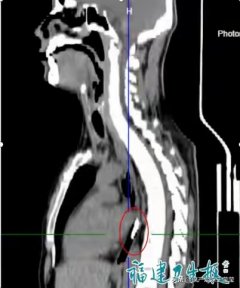

打火机 老邓 胃部 2025/11/25

打火机 医生 钳子 2025/11/24

打火机 胃镜 异物钳 2025/11/24